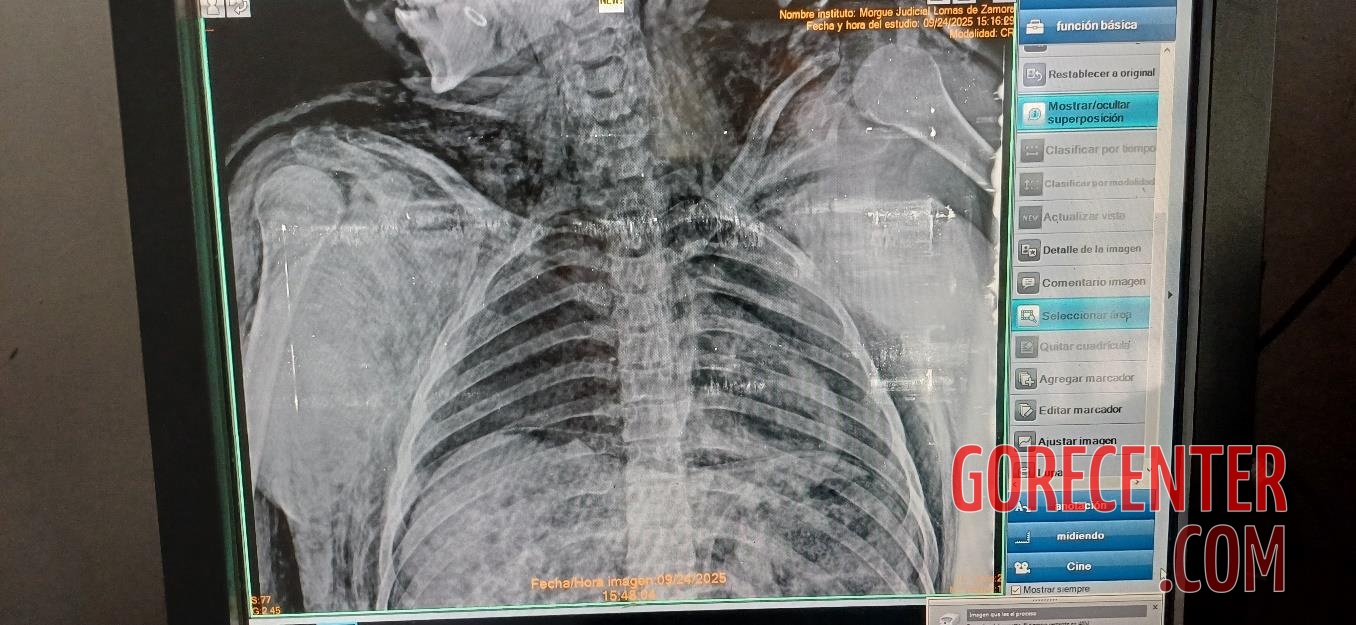

BRENDA’S AUTOPSY:

MORENA’S AUTOPSY:

LARA’S AUTOPSY: